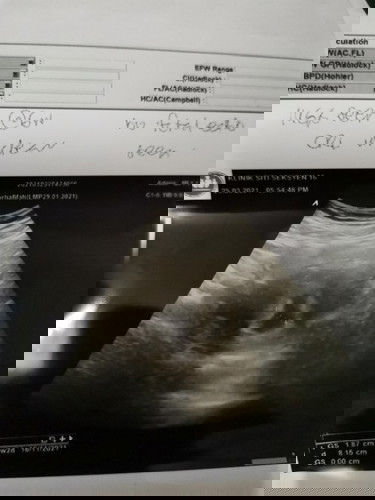

Pregnt 7m6h, tapi scan hanya nampak kantung 6m,tak nampk baby or heartbeat.. Rasa down sangat.. 😢First scan 5 weeks, xnmpk kantung, skrg da nmpk tu pon doc ckp 6w,xnmpk baby.. 3 weeks lg appmnt.. Hope ade hrpn..

Mungkin conception time lambat lagi dr kiraan period sis. Sy punya klau ikut lmp 8 wks xnampak lg kantung baby. Masa 10w+ scan kt klinik swasta br nampak kantung. Kecik lg br dlm 5w. Skrg dh nak masuk 5 bulan dh..

ikut scan tu sis baru betul usia kandungan . normal sis mcm tu . 6w mmg baru nampak kantung je tunggu 8w ke atas baru nampak janin sekali heartbear bby